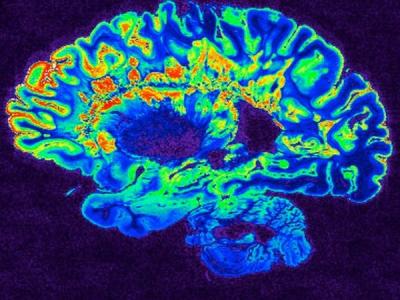

In a recent study, researchers discovered what type of neural mechanisms are the basis for emotional responses to music.

Altogether 102 research subjects listened to music that evokes emotions while their brain function was scanned with functional magnetic resonance imaging (fMRI). The study was carried out in the national PET Centre.The researchers used a machine-learning algorithm to map which brain regions are activated when the different music-induced emotions are separated from each other.

- Based on the activation of the auditory and motor cortex, we were able to accurately predict whether the research subject was listening to happy or sad music. The auditory cortex processes the acoustic elements of music, such as rhythm and melody. Activation of the motor cortex, then again, maybe related to the fact that music inspires feelings of movement in the listeners even when they are listening to music while holding still in an MRI machine, says Postdoctoral Researcher Vesa Putkinen.

The researchers also discovered which brain regions are activated when the research participants watched videos that evoke strong emotions and tested whether the same regions were activated when the participants were listening to music that evokes emotions.

The results suggest that the emotions evoked by films and music are partially based on the operation of different mechsms in the brain.

- Films, for instance, activate the deeper parts of the brain that regulate emotions in real-life situations. Listening to music did not strongly activate these regions nor did their activation separate the music-induced emotions from each other. This may be due to the fact that films can more realistically copy the real-life events that evoke emotions and thus activate the innate emotion mechsms. As for the music-induced emotions, they are based on the acoustic characteristics of music and coloured by cultural influences and personal history. Traditionally, music-induced emotions have been studied through classical instrumental music.